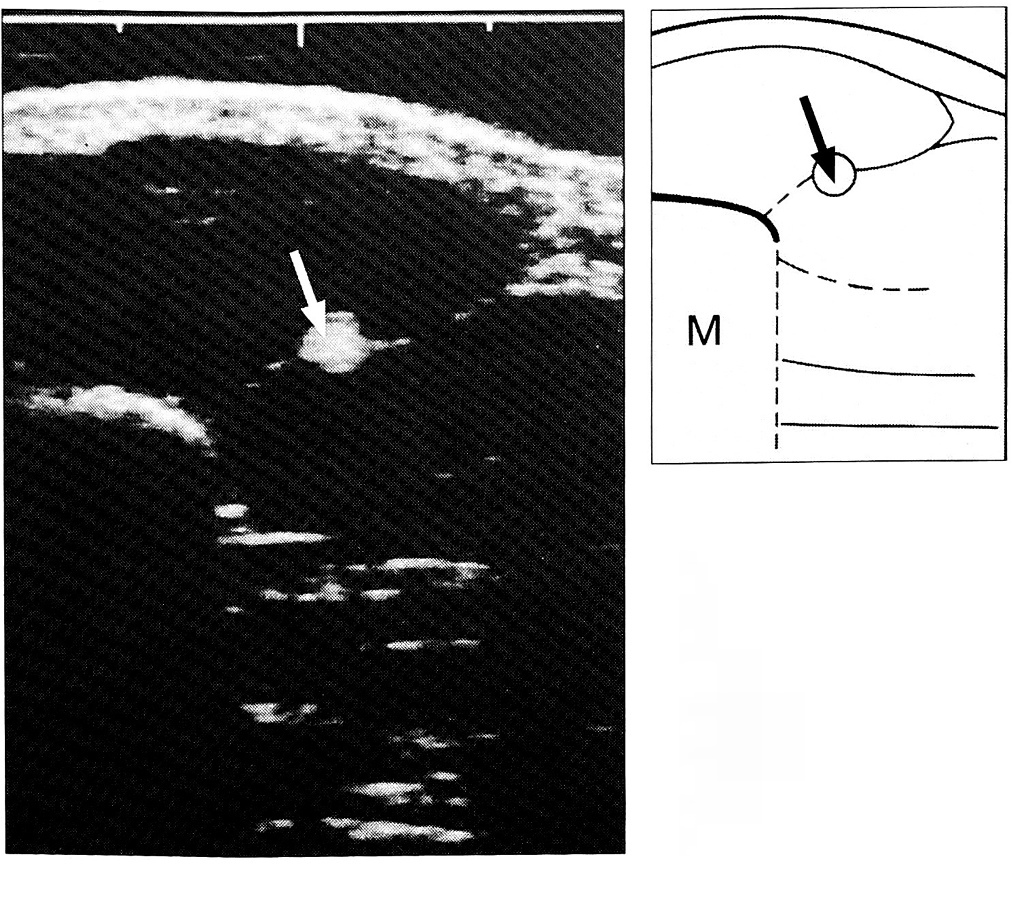

Поперечное сканирование. Поперечное сечение сухожилий также эхогенно. При поперечном сканировании кисти и пальцев (рис. 2) на экране монитора определяются: 1) кожа в виде гиперэхогенной полосы (обычно изогнутой); 2) гипоэхогенная подкожная жировая клетчатка или еще менее эхогенные мышцы с мелкими точечными либо штриховыми вкраплениями; 3) сухожилие в окружении жировой клетчатки или мышц в виде овального пятнистого образования с сетевидной текстурой; 4) фрагмент яркой эхогенной линии надкостницы.

Рис. 2. Поперечная сонограмма сухожилия (стрелка) длинного сгибателя I пальца в области тенара (М — I пястная кость).